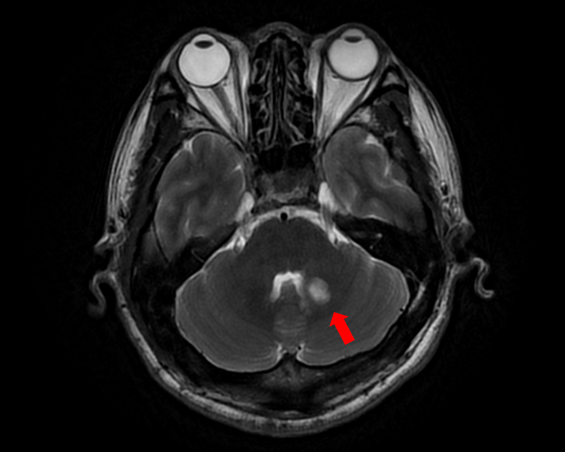

随着患者高先生颅内中脑左侧、左侧小脑两处病灶的顺利切除,国际神经外科医生集团专家已累计在苏大附四院完成了第100例高难手术。这标志着我院在神经外科国际化合作交流方面取得了里程碑式的成果,也为众多疑难脑肿瘤患者带来了新的希望。